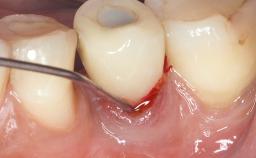

Paolo Casentini demonstrates that peri-implantitis can be successfully treated even at an advanced stage. He discusses a case in which the existing implants and prostheses were both retained while regenerating the defect and creating a band of keratinized tissue. A 69-year-old female patient was referred by her general dentist for evaluation of a recurrent infection at previously placed and restored implants in the posterior left mandible. The patient’s chief complaint was recurrent swelling and pain in the molar region of the left posterior mandible with discomfort during brushing in the same area. The patient reported receiving two implants (36 and 37) nine years earlier.